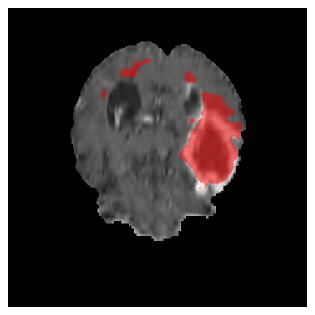

Appendix A Qualitative results

Figure 5 illustrates the segmentation evolution for the same BRATS patient in S2 sequence. The key difference here is that the best buffer-free strategy is EWC (=1), and training on BRATS data starts from episode 2 instead of episode 1 as BRATS is encountered at episode 2 in S2. The cumulative approach retains segmentation across episodes but continues to generate false positives, which become even more pronounced in the final episode. The naive approach, lacking a CL mechanisms, completely overrides previous knowledge, leading to failed segmentation in later episodes. EWC (=1) approach initially maintains segmentation but experiences a sharp decline in episode 4, where it fails to segment the tumor. In the final episode, it undersegments the lesion, missing a significant portion of the tumor. In contrast, the proposed approach consistently preserves segmentation across episodes. While initially introducing false positives, it gradually refines predictions, retaining the tumor region while minimizing misclassifications. It maintains clear tumor delineation by the final episode, demonstrating effective knowledge retention and adaptability throughout training.